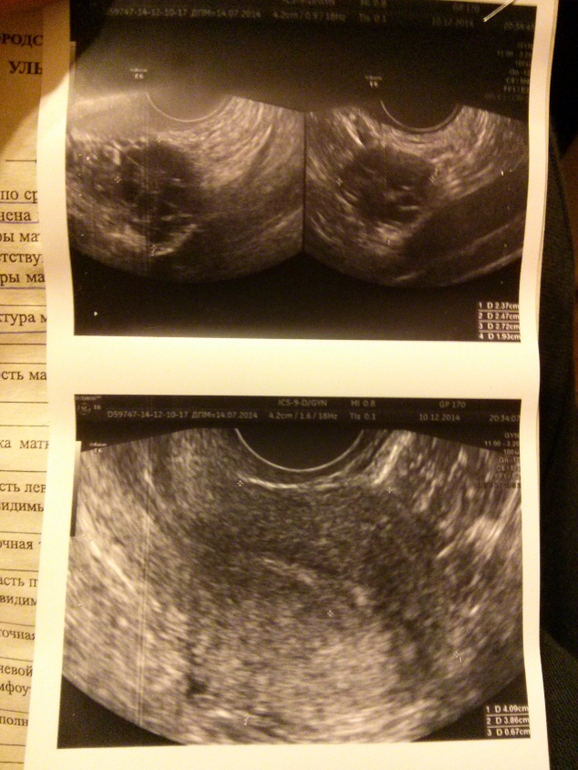

А сегодня пошла на УЗИ... где меня не обрадовали. Причем пошла на плановое, чтобы потом к врачу в понедельник. Думала просто опишут что там все в порядке (а только на гормональном не очень). Но не тут то было. Узистка очень хорошая женщина (что меня порадовало для нашей ЖКХ). Сначала подумала что я по Б, я сказала что пока к сожалению нет. Она:" Ну ничего, это пока...". В общем сначала она спросила не ставили ли мне когда-либо эндометриоз (на моем веку была эрозия (прижигали), полип (чистили) и поликистоз (вот от куда и пила больше 10-ти лет ОК)). Я ответила небыло, она сказала что матка такая ячеистая, но сказала что пока не будет ставить мне этот эндометриоз. Потом сказала что не нравятся ей яичники.. и да.. итог - мультифолликулярные яичники... тоже такого не было.. сказать что мне стало печально - ничего не сказать. Никогда больше не буду пить ОК! Сказала что О не будет в этом цикле точно (не зря БТ 7-й день 36,6 у меня). Но коричневая мазня которая идет тоже 7-й день это М, раньше такое бывало до приема ОК. Сказала что с таким диагнозом тоже беременеют, но нужен какой то эмоциональный всплеск. Спросила сколько мы с мужем, я сказала 3 года. На что она ответила что это конечно уже не пик страстей)) Повеселила)) Мужу после этого сказала купи мне шубу мол, чтобы пик страстей вызвать)))

В общем шутки шутками а факты остаются фактами... Сгребаю в кучку все анализы (еще спермограмму сдадим на днях) и иду к врачу, посмотрим что она еще скажет. Кстати УЗИстка посоветовала попить фольку (пью), омега 1 (пью), аэвит и гинекохель. И телефон свой оставила. Сказала попей геникохель и посмотри что будет... Но дело в том что я так не хочу ждать, ведь может быть ничего и не будет(((